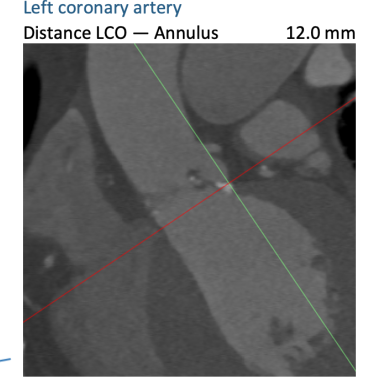

FEops评估冠脉风险

根据FEops报告上的左右冠脉CT截面得知RCA Height:12.0mm、LCA Height:12.0mm,具有一定冠脉闭塞风险,通过观察模拟植入后瓣叶与冠脉开口的位置关系,得知该患者冠脉闭塞风险比较高,建议行冠脉保护确保手术安全。